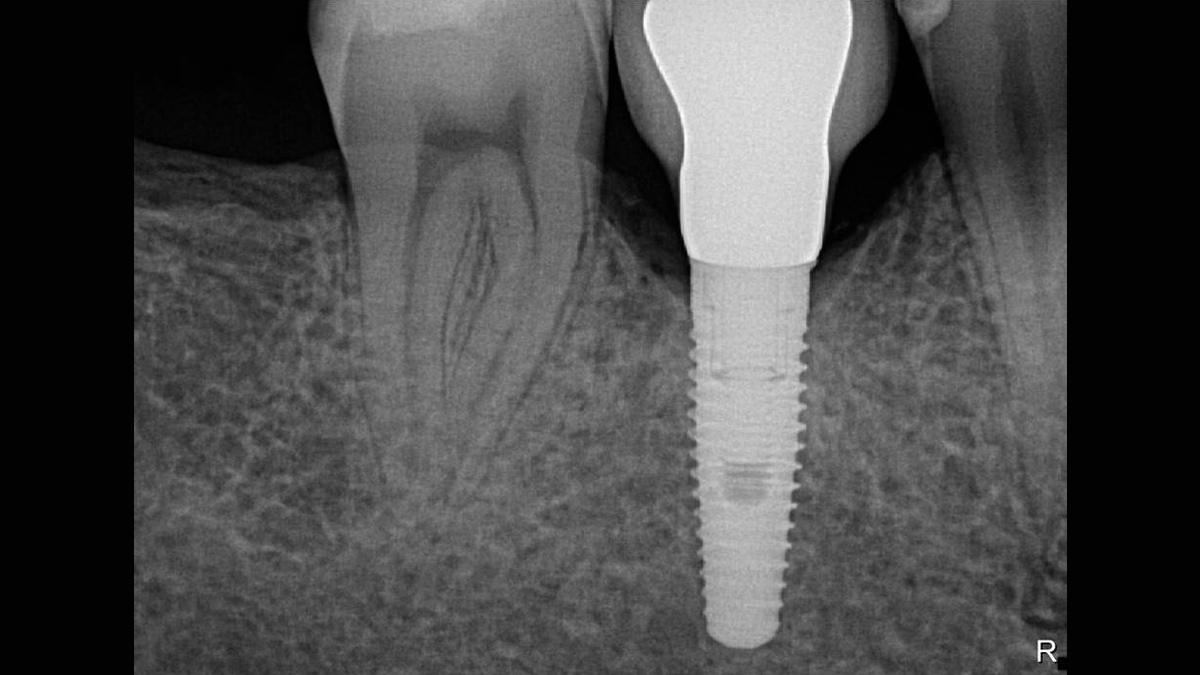

Xios XG Supreme proporciona una resolución teórica de 33 pl/mm y un tamaño de píxel de 15 μm que ofrece una excelente calidad de imagen sin el tiempo de espera adicional causado por un proceso de revelado o escaneo.

La excepcional calidad de las imágenes es solo el comienzo con los sensores intraorales Xios XG Supreme. El deslizador de nitidez dinámica le permite ajustar las configuraciones de su diagnóstico en términos de nitidez. Hay disponibles opciones adicionales del deslizador para modificaciones de brillo y contraste. Después de la configuración, las imágenes se muestran de manera eficiente para mejorar sus capacidades de diagnóstico, lo que le ahorra tiempo valioso. Un solo clic del mouse le permite obtener la imagen correcta para cada situación de tratamiento y mejor soporte clínico.

Los sensores Xios XG Supreme tienen cinco opciones diferentes de filtro: odontología general, endodoncia, periodoncia, restauración y caries. Estas vistas clínicamente específicas están diseñadas para optimizar su diagnóstico, mejorando la imagen para satisfacer sus necesidades.